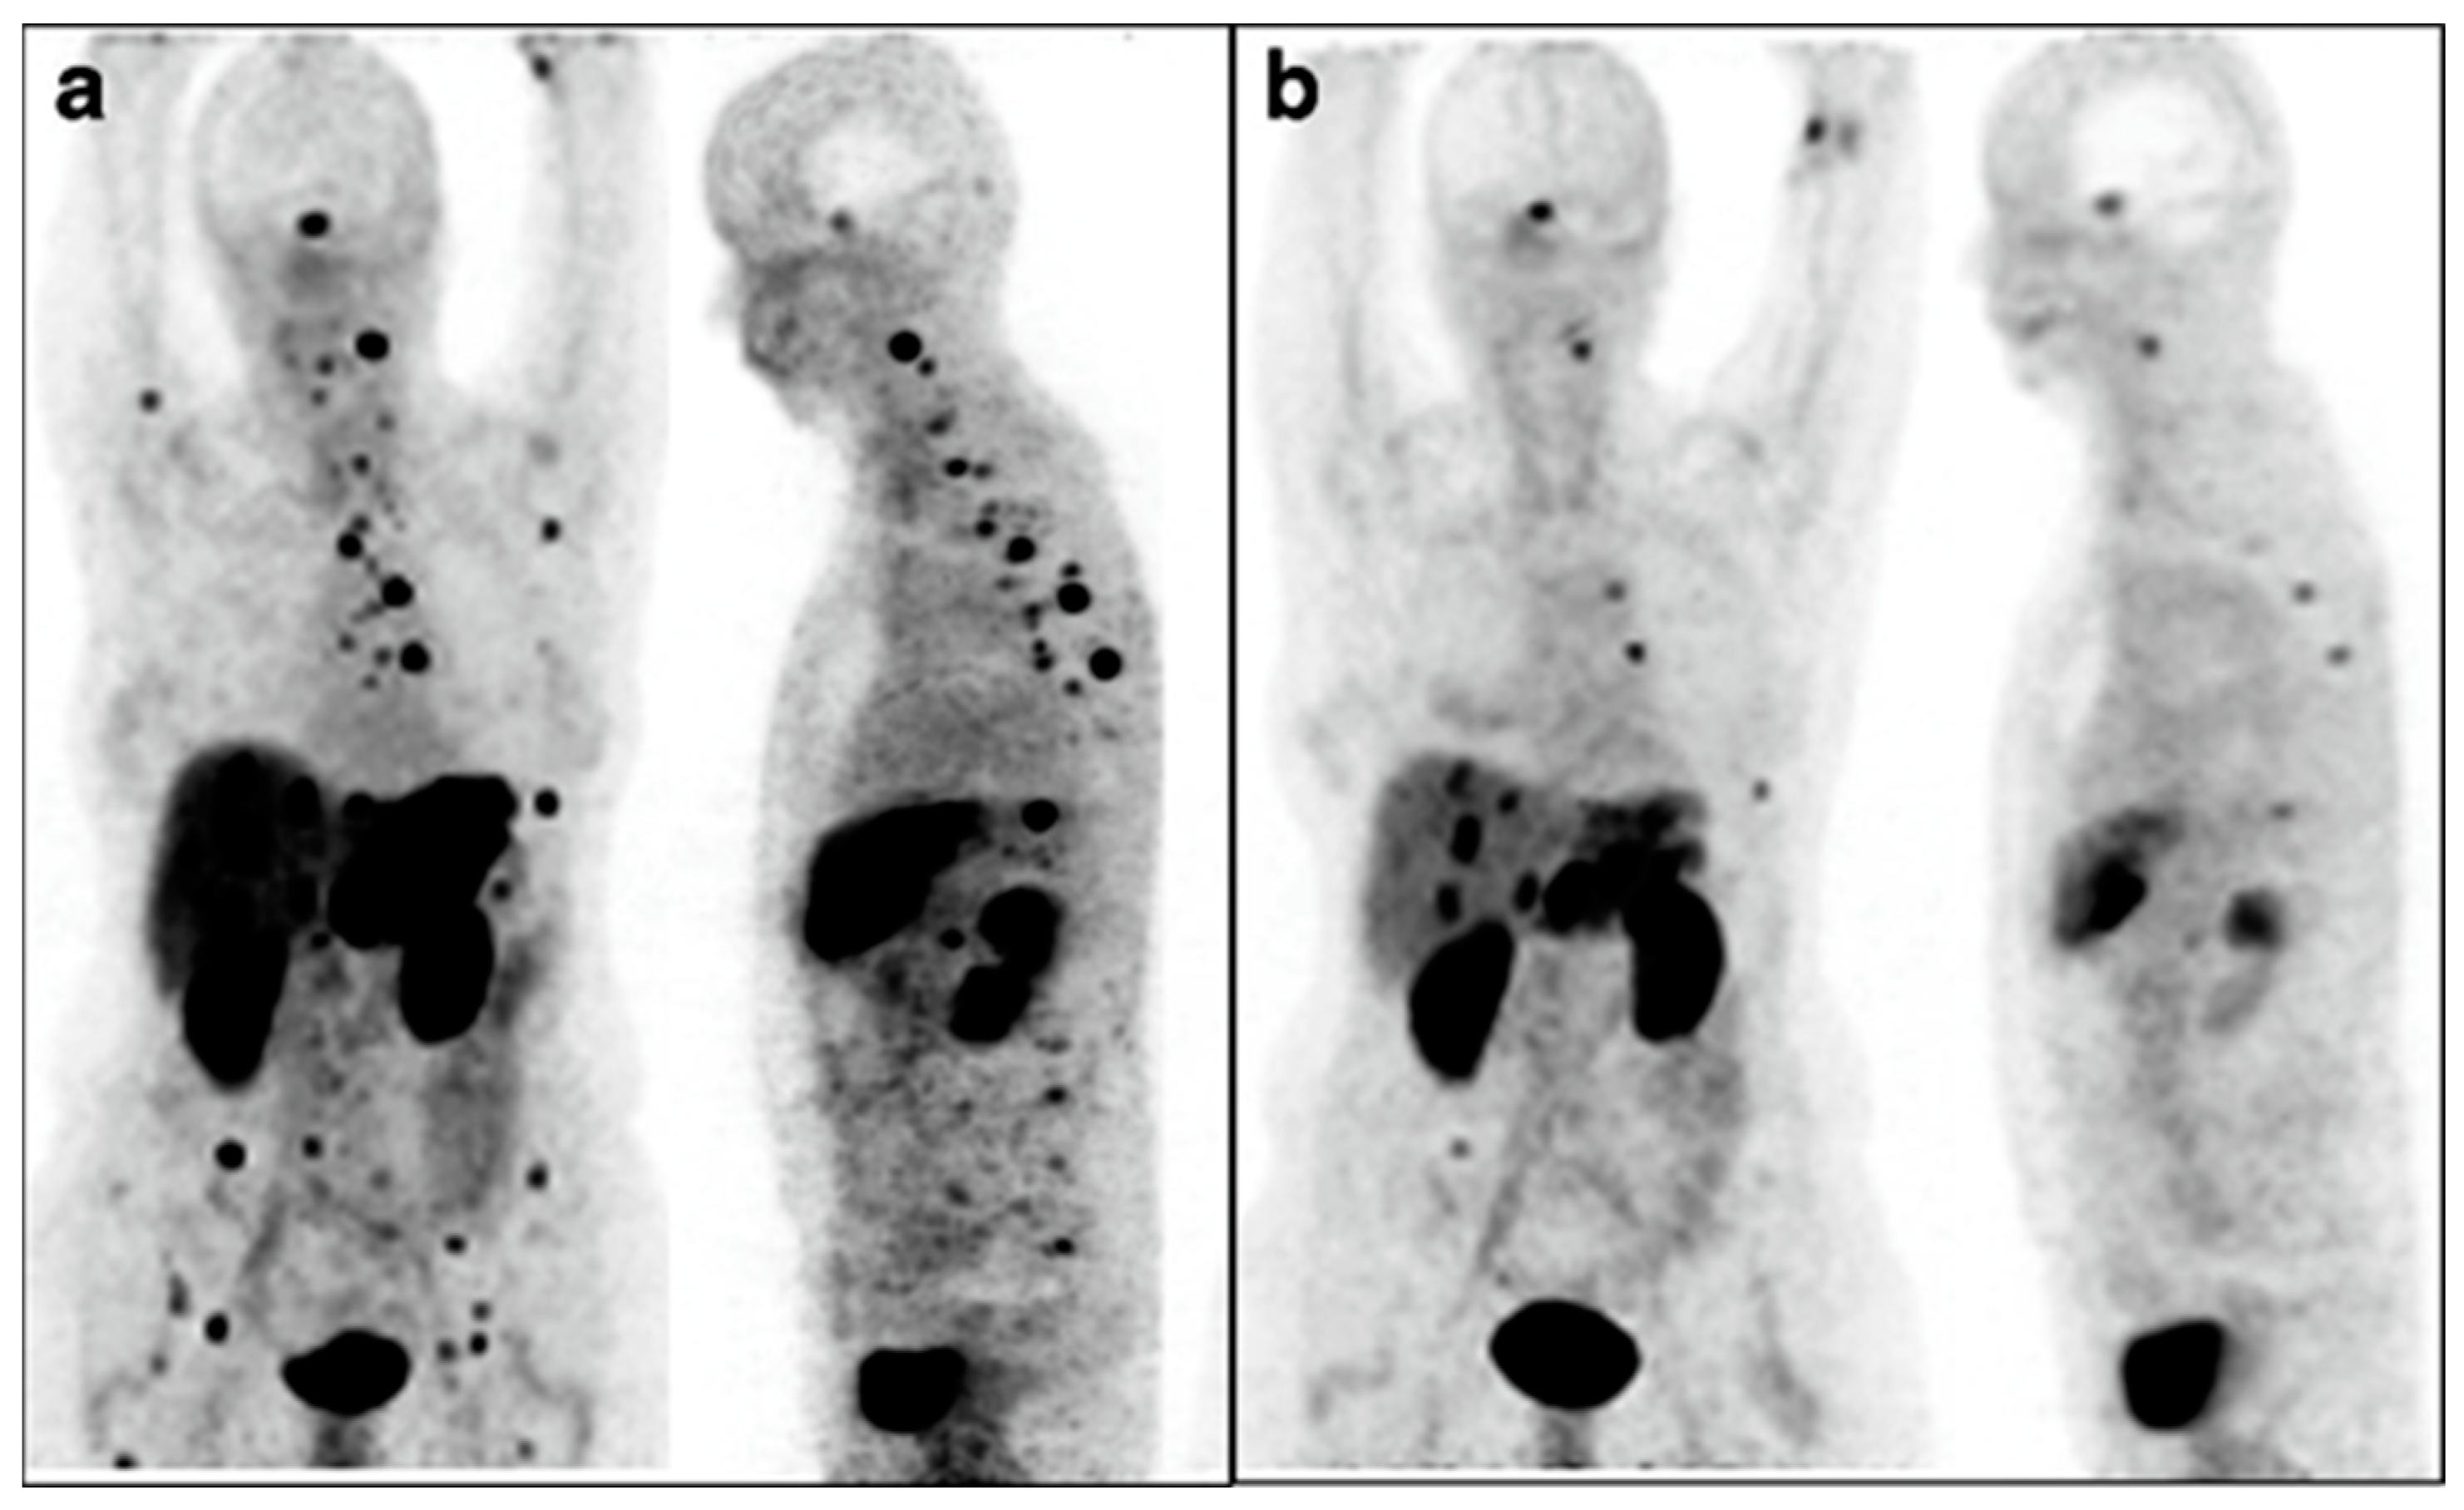

Figure 5.

Alpha (α)-particle therapy overcomes β-resistant cancer. This imaging was performed using Ga-68-PSMA-11 PET/CT scanning. Kratochwil, C. et al. [49] reports, “In comparison to initial tumor spread (A), restaging after 2 cycles of β-emitting 177Lu-PSMA-617 presented progression (B). In contrast, restaging after second (C) and third (D) cycles of α-emitting 225Ac-PSMA-617 presented impressive response.” This research was originally published in The Journal of Nuclear Medicine [49].

The strongest example supporting the use of a radioisotope with α-particle emissions delivered by an alternate route was from Kratochwil et al., who used Bi-213-DOTATOC-delivered IA to overcome previous resistance to Y-90-DOTATOC therapy [55]. Patients underwent an interventional procedure to deliver therapy to the hepatic artery, meaning the treatment went to most of the liver. Further, the leakage of therapy into the systemic system allowed for treatment of disseminated sites, which is shown in Figure 6. While this study did not compare IA to IV as closely as others, it represents a major advancement in understanding both α-particle therapy and IA delivery of radiopharmaceuticals.

Figure 6.

Intra-arterial Bi213-DOTATOC overcomes Y90-DOTATOC resistance. Ga-68-DOTATOC-PET imaging shows bulky liver disease and widespread lesions before treatment (a). Reduction in both primary liver and metastatic disease was seen on imaging six months after administration of Bi-213-DOTATOC into the common hepatic artery (b). This research was originally published in the European Journal for Nuclear Medicine and Molecular Imaging [55]. https://creativecommons.org/licenses/by/4.0/legalcode, accessed on 1 February 2023.